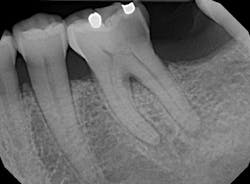

Upon radiographic analysis, noted caries encroaching the pulp chamber, thickening of the PDL on the mesial root, and the start of apical osseous breakdown on the distal root. Pulp chamber and canals deemed slightly constricted and pulp stone recognized towards the distal.

Pulpal diagnosis: Irreversible pulpitis

Periapical diagnosis: Symptomatic apical periodontitis